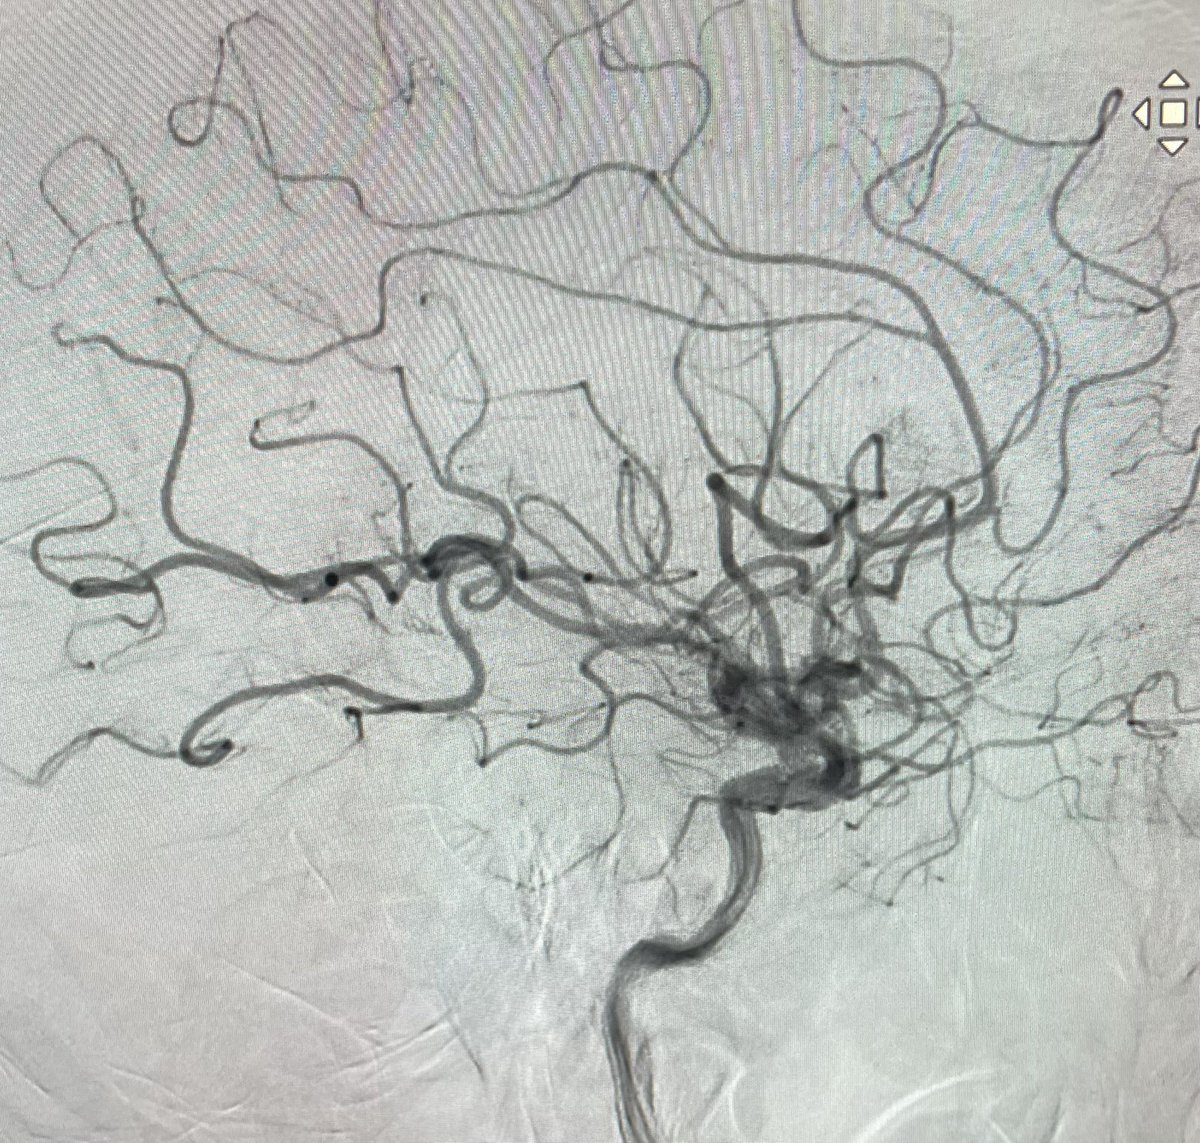

El Dr. Carlos Pérez@Justcharly9, nos resume en menos de 15 minutos los dos principales ensayos clínicos que comparan tratamiento Endovascular VS Quirúrgico (ISAT, IBRAT) de aneurismas rotos.